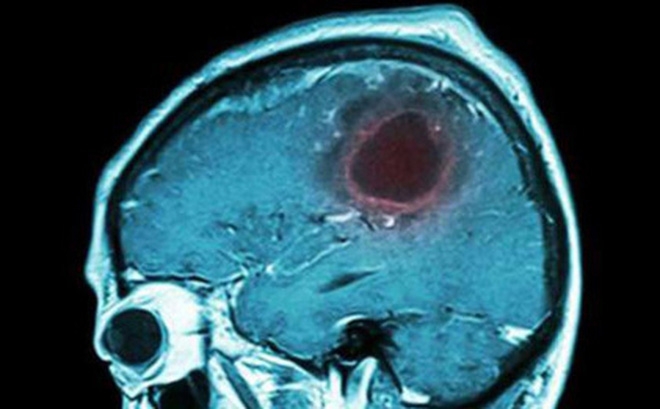

Theo các nhà khoa học, u não là thuật ngữ thường được dùng có tính cách quy ước để chỉ các khối u hình thành ở trong sọ não. Trên thực tế, u não thường phát hiện muộn nên biện pháp xử trí gặp rất nhiều khó khăn, tiên lượng xấu và hậu quả để lại cũng khá tồi tệ. Đặc điểm của u não U não bao gồm nhiều loại khác nhau, trong đó u trong mô não chiếm trên dưới...